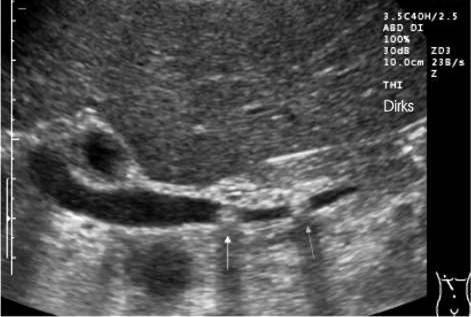

Рисунок 1 – Классическое УЗИ (расширение холедоха и визуализация двух конкрементов в его дистальной части)

• Увеличение диаметра холедоха более 8 мм, а внутрипеченочных протоков более 4 мм;

• Увеличение и деформация желчного пузыря, неоднородное содержимое, мелкие конкременты, визуализация камня в протоке;